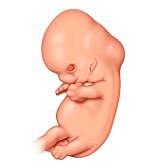

• Caracterización

35

Caracterización

El embrión ya tiene características humanas evidentes